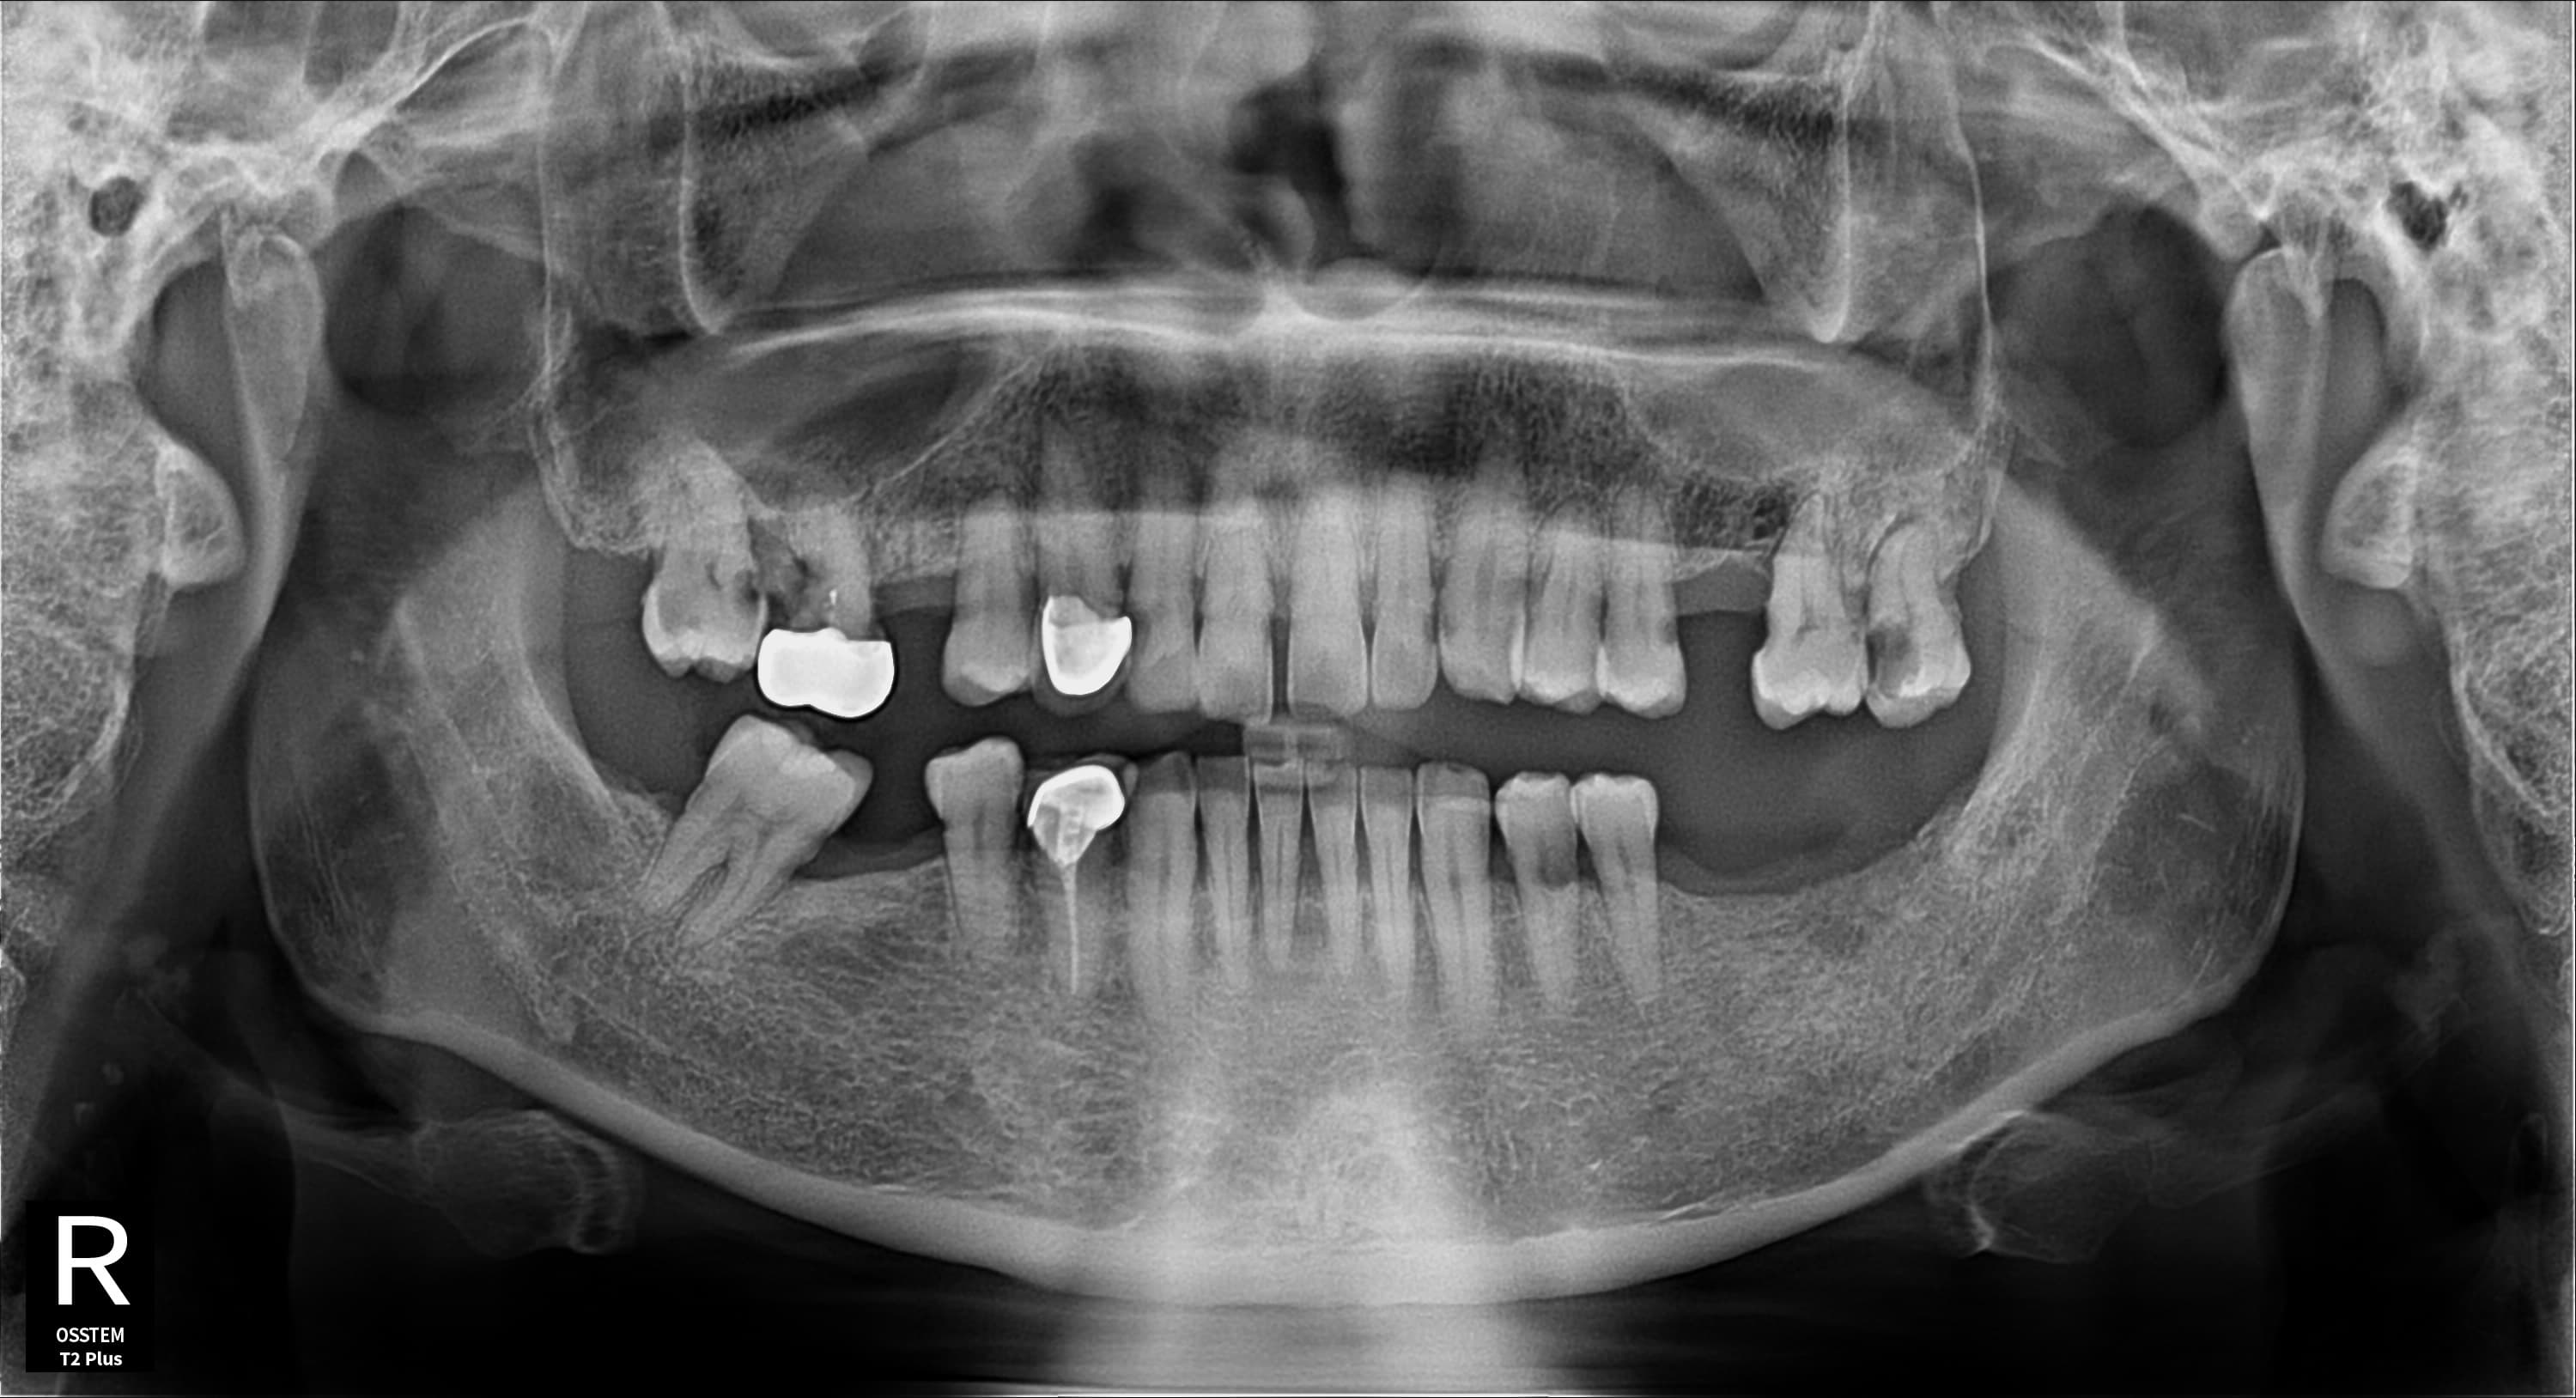

Before

다수 임플란트 · 엑스레이 · 지●● · 남성